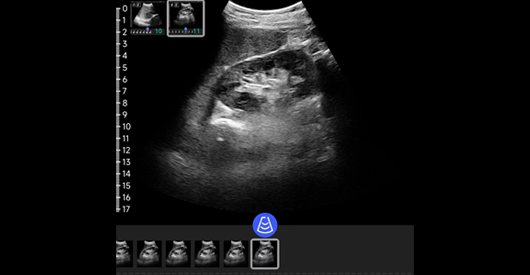

肝脏

阵元基数:128。信号通道:64。